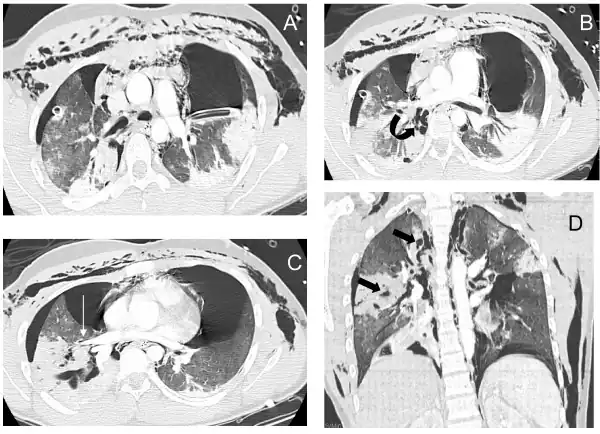

A patient with traumatic complete disruption of the right bronchus. Computed tomography scan following emergency chest tube drainage. Axial 1.25 mm thick sections with a lung window. (a) Persistent bilateral pneumothorax, pneumomediastinum and extensive subcutaneous emphysema. (b) Multiple lucencies around the right bronchial tree (curved arrow) precluding the correct recognition of the bronchial rupture. (c) The Macklin effect around the right lower pulmonary vein (white arrow). (d) Coronal view demonstrating multiple areas of alveolar consolidation in the right upper and lower lobes: intraparenchymal lucencies resulting from lung lacerations are visible on the right side (thick arrows).

Chest x-ray is the initial imaging technique used to diagnose TBI.[17] The film may not have any signs in an otherwise asymptomatic patient.[15] Indications of TBI seen on radiographs include deformity in the trachea or a defect in the tracheal wall.[17] Radiography may also show cervical emphysema, air in the tissues of the neck.[2] X-rays may also show accompanying injuries and signs such as fractures and subcutaneous emphysema.[2] If subcutaneous emphysema occurs and the hyoid bone appears in an X-ray to be sitting unusually high in the throat, it may be an indication that the trachea has been severed.[4] TBI is also suspected if an endotracheal tube appears in an X-ray to be out of place, or if its cuff appears to be more full than normal or to protrude through a tear in the airway.[17] If a bronchus is torn all the way around, the lung may collapse outward toward the chest wall (rather than inward, as it usually does in pneumothorax) because it loses the attachment to the bronchus which normally holds it toward the center.[6] In a person lying face-up, the lung collapses toward the diaphragm and the back.[23] This sign, described in 1969, is called fallen lung sign and is pathognomonic of TBI (that is, it is diagnostic for TBI because it does not occur in other conditions); however it occurs only rarely.[6] In as many as one in five cases, people with blunt trauma and TBI have no signs of the injury on chest X-ray.[23] CT scanning detects over 90% of TBI resulting from blunt trauma,[3] but neither X-ray nor CT are a replacement for bronchoscopy.[6]